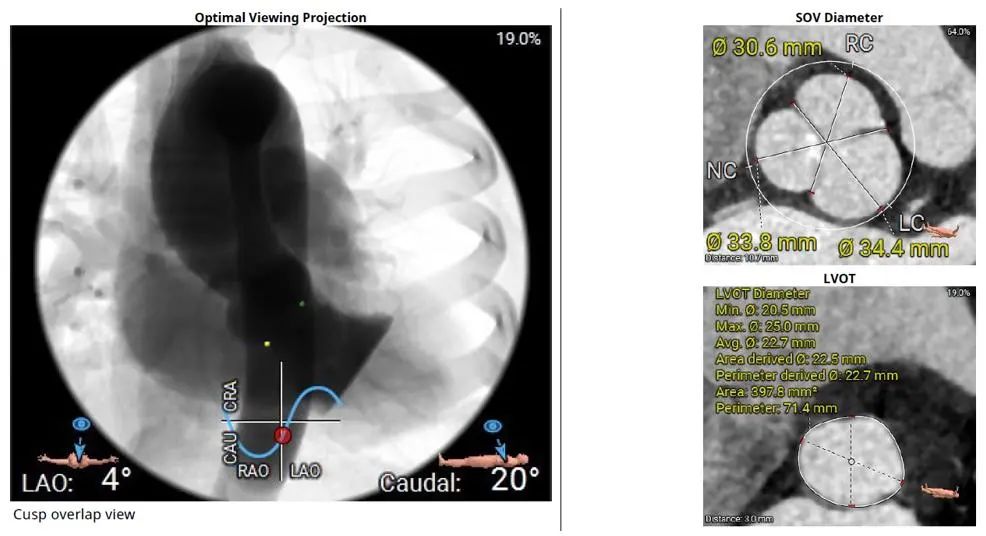

2021年8月3日,浙大二院王建安教授成功使用美敦力公司的最新一代EVOLUT PRO瓣膜系统为一位外科手术高危患者完成经导管主动脉瓣置换术手术,这是该产品在中国大陆的首次应用,也是EVOLUT PRO中国上市前临床研究入组的第一例病例。

术前CT评估